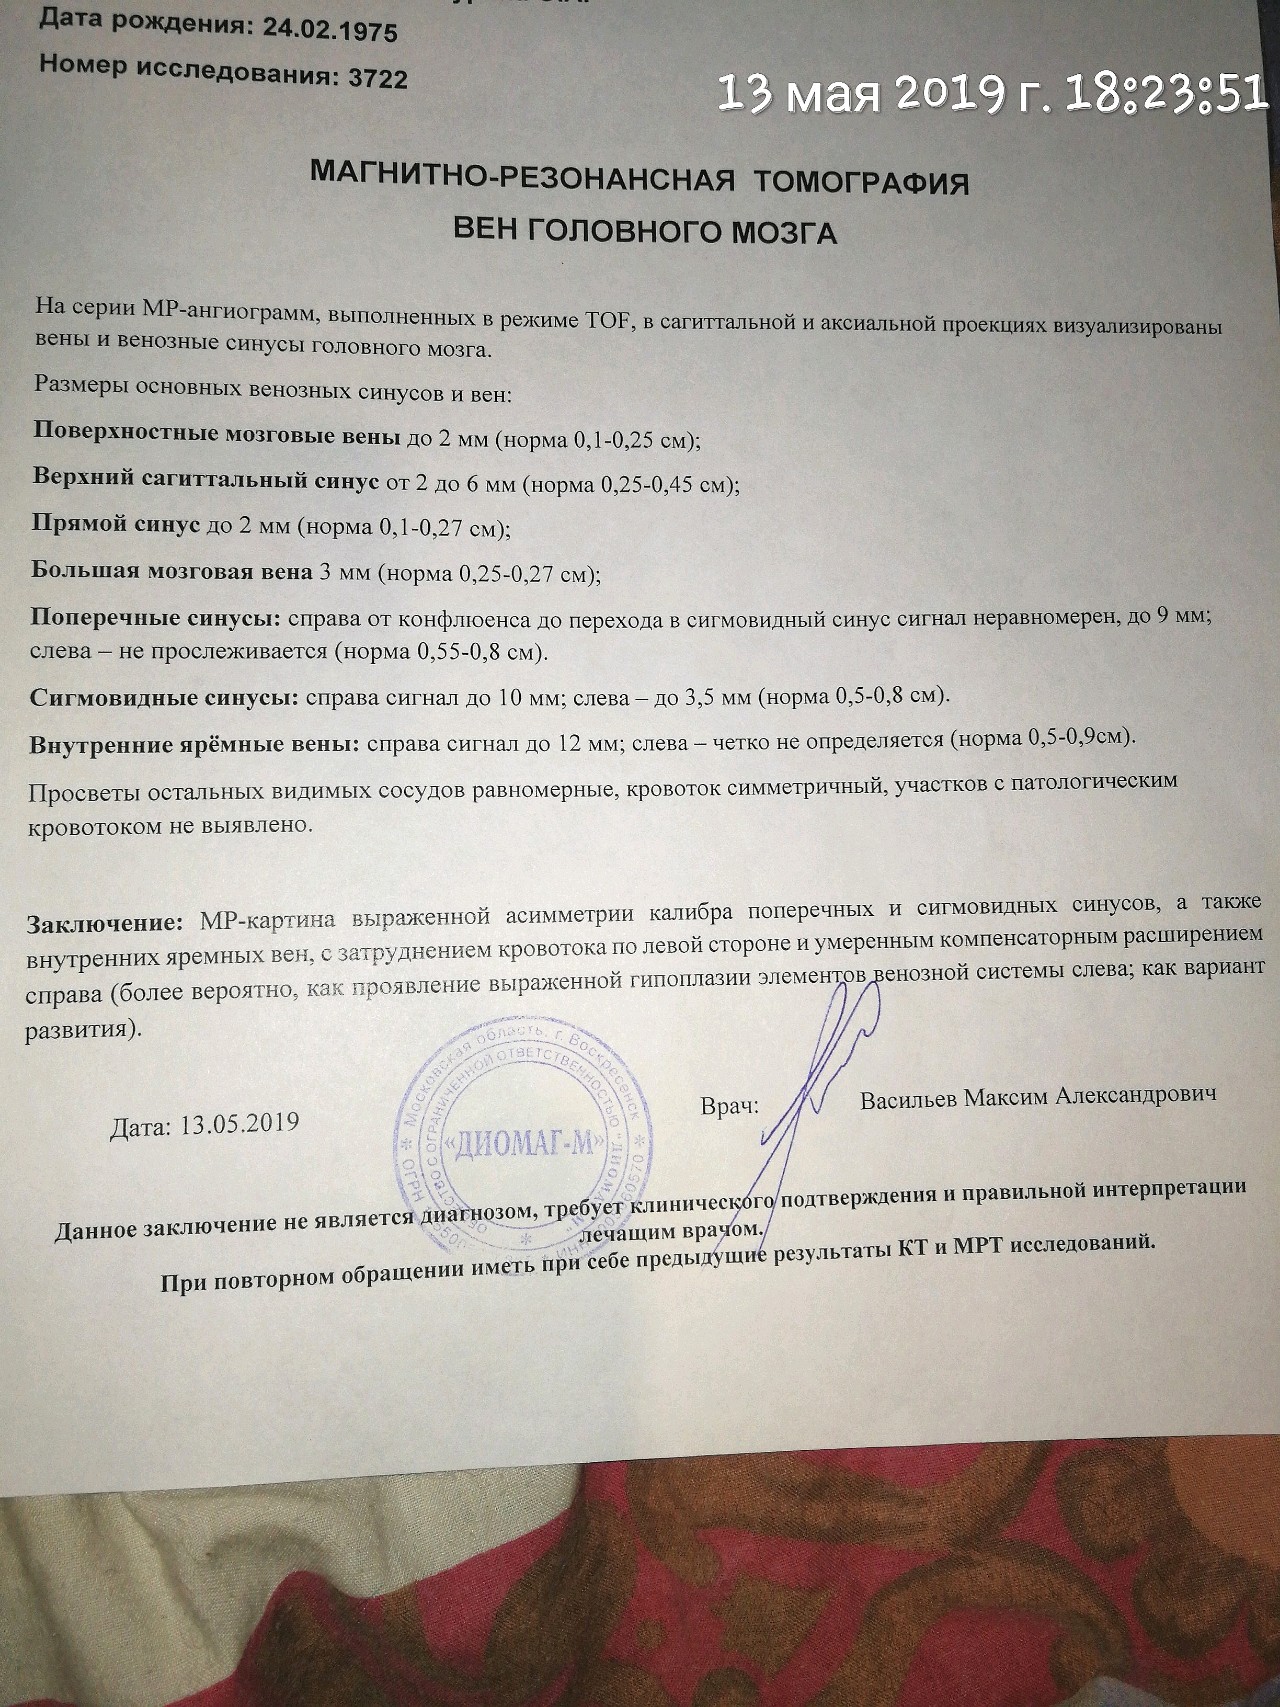

МРТ головного мозга: Расшифровка снимков и Интерпретация

Раздел: Визуальные уроки